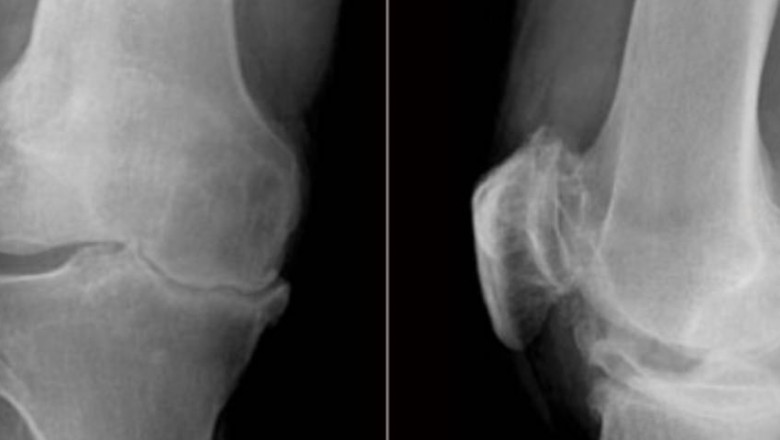

By far Osteoarthritis, is the most common joint disorder worldwide. It is truly universal condition, affecting both sexes and all races. Evidences

By far Osteoarthritis, is the most common joint disorder worldwide. It is truly universal condition, affecting both sexes and all races. Evidences suggest that prevalence rises from 1 per cent below the age of 30 years to over 50 per cent in people above the age of 60.

It is most obvious that Osteoarthritis increases with age, so is it simply an expression of senescence? No, it occurs with significant frequency in certain joints and certain areas of a particular joint, while all the other joints are commonly spared. Joints such as Hip, Knee, Base of thumb and Spine are more frequently involved than others, with Knee joint being the commonest.